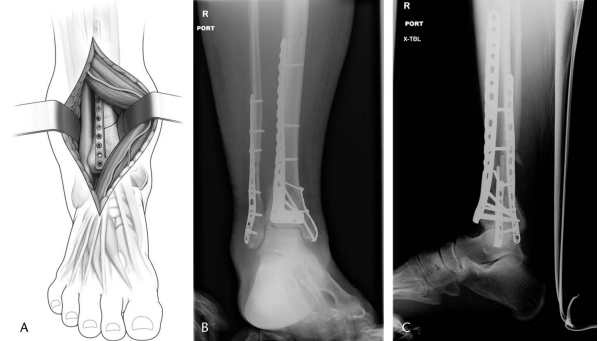

一旦处理了腓骨骨折,如前所述,前外侧切口以踝关节为中心,远端平行于第四跖骨,近端位于胫骨和腓骨之间(图 1)。切口近端延伸超过踝关节 7 厘米以上会破坏前间室肌肉的起点。远端,切口终止于距舟关节稍远侧。需要切口的远端范围来直视穹顶后部和应用通用撑开器。

图 1. (A) 示意图和 (B) 临床照片,显示扩大前外侧显露的切口,以踝关节为中心,远端平行于第四跖骨,近端位于胫骨和腓骨之间。

图 7. 示意图 (A)、前后位 (B) 和侧位 (C) 影像显示通过前外侧显露应用前外侧接骨板,并采用经皮近端螺钉固定。